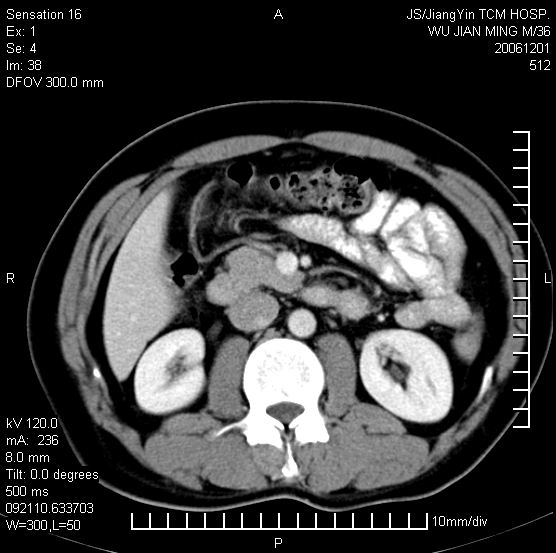

以下是引用dyqct在2006-12-1 21:17:00的发言:[br]左心缘旁及后肋膈窦区见巨大椭圆形混杂密度肿块,周围见大小不等斑片状钙化,内部无强化,周围包膜轻度强化,心脏明显受压变形,即明显占位效应,肿块广基与心包、膈相连。肝、脾内、肝门见多数小结节状钙化影。[br]考虑:1、左心缘旁及后肋膈窦区慢性包裹性胸膜炎(结核性);[br] 2、肝、脾及肝门淋巴结核已钙化。[br]

以下是引用zrs在2006-12-2 17:28:00的发言:[br]肺内、肝脾内虽有钙化,但不支持结核性胸胸膜炎包裹,而支持寄生虫感染![br][br]

以下是引用zyx168在2006-12-2 10:10:00的发言:[br][br]肝脾肺内多发钙化灶